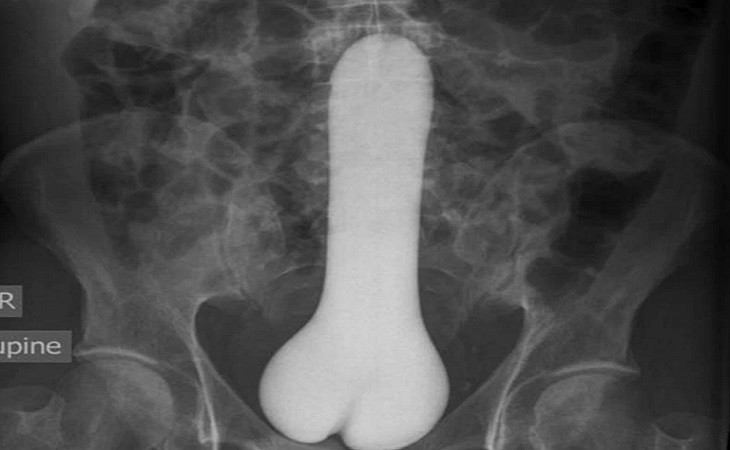

Но лидируют в данном списке, по понятным причинам, секс-игрушки. Один из врачей предложил продавать подобные вещи со специальными шнурами для удаления, чтобы облегчить труд медицинских работников. При этом доктора добавили, что секс-игрушки безопаснее, чем различные предметы из бытового обихода.

В большинстве случаев посторонние предметы врачам приходилось удалять хирургическим путем.